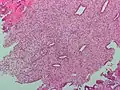

(A) proliferative endometrium (Left: HE × 400) and proliferative endometrial cells (Right: HE × 100)

(B) secretory endometrium (Left: HE × 10) and secretory endometrial cells (Right: HE × 10)

(C) atrophic endometrium (Left: HE × 10) and atrophic endometrial cells (Right: HE × 10)

(D) mixed endometrium (Left: HE × 10) and mixed endometrial cells (Right: HE × 10)

(E): endometrial atypical hyperplasia (Left: HE × 10) and endometrial atypical cells (Right: HE × 200)

(F) endometrial carcinoma (Left: HE × 400) and endometrial cancer cells (Right: HE × 400).